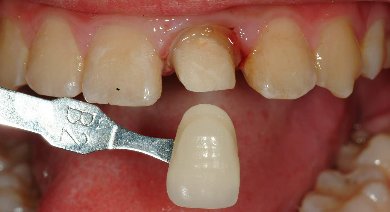

根管內稍做修形放入玻璃纖維 , 修形成全瓷冠需要的牙齒形狀,以雙線排齦方式印模(見圖四) , 並以數位照相及比色機比色(圖五)

圖五 |